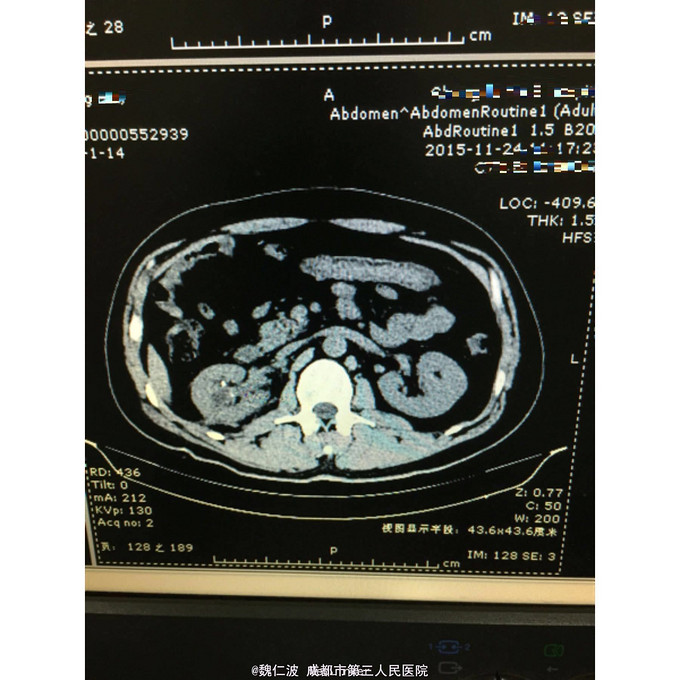

右侧输尿管结石碎石术后3月,发现右侧输尿管上段闭锁4天 3月前因右侧输尿管上端结石行输尿管软镜钬激光碎石,术后恢复可,但拍石稍差,1月后取支架管,术后2月复查右侧肾积水1厘米,3月复查积水5Cm,外院行右肾穿刺造瘘术,发现右侧输尿管上端闭锁,遂来我院。

右侧输尿管上端闭锁,右肾结石,右侧输尿管上端结石 经抗感染治疗后,行开放狭窄段切除,输尿管吻合术,安置F8输尿管支架管。

输尿管结石常合并息肉形成,结石处理后往往伴随着狭窄问题,会给临床医生带来不小麻烦。术前后均需充分告知,并定期随访。 但有无好的处理方式,可以减少术后狭窄的发生呢?谢谢大家不吝赐教!